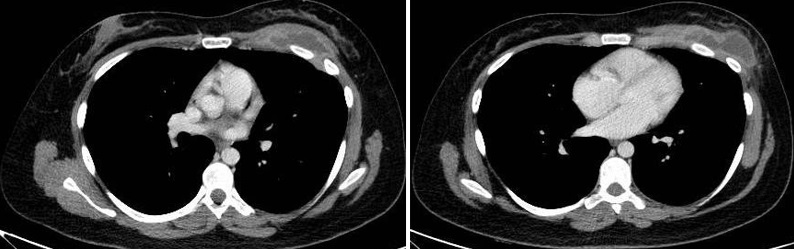

Paciente femenina de 26 años de edad, sin antecedentes patológicos de relevancia, sin dosis de vacuna BCG. Cursa con cuadro clínico de ocho meses de evolución, caracterizado por dolor en región pectoral izquierda intermitente, que se exacerba a la inspiración profunda. En el último mes se palpa masa indurada dolorosa a la palpación a nivel del cuadrante inferior interno de mama izquierda, motivo por el cual se realiza ecografía de partes blandas, donde se observa a nivel retropectoral en íntimo contacto con la parrilla costal imagen hipoecogénica de bordes delimitados, avascular al Doppler color por lo cual se solicita TC de tórax con EV. En ella se observa en topografía del cuarto espacio intercostal, imagen hipodensa con realce periférico tras la administración del contraste que desplaza por efecto de masa el parénquima pulmonar adyacente y se proyecta a la pared torácica anterolateral izquierda; mide 40 mm x 55 mm. Además, se visualiza otra imagen de similares características de base pleural en contacto con el octavo arco costal posterior izquierdo que mide 6 mm x 11 mm.

Cuatro meses posteriores a la PAAF la paciente refiere persistencia de dolor y aumento de tamaño de la masa asociado a eritema en región mamaria, por lo cual se realiza TC de tórax con contraste EV donde se observa imagen hipodensa ya conocida, con realce periférico tras la administración de contraste, con aumento de tamaño y bordes lobulados.